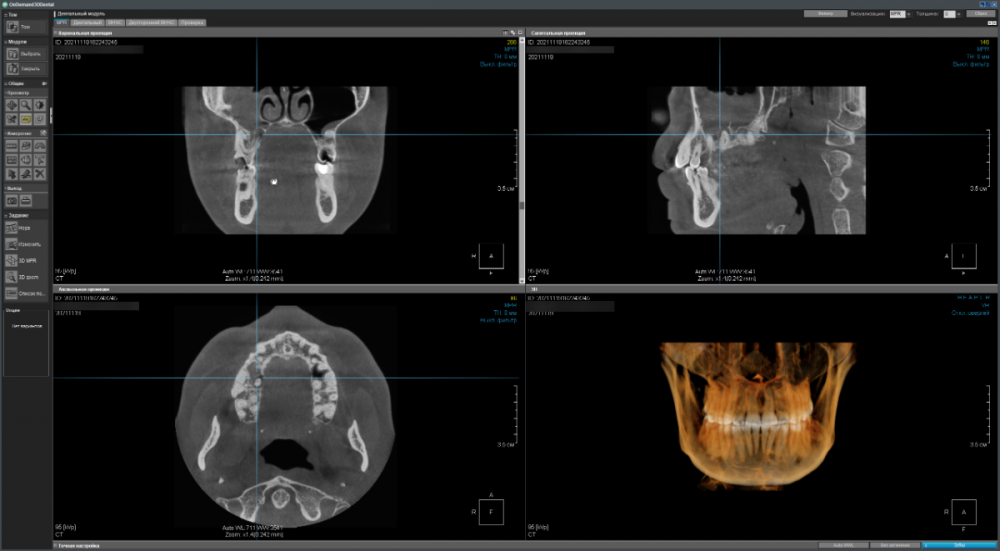

Имеется два сильно запущенных зуба на верхней челюсти справа - хотелось бы понять имеет ли смысл пытаться вылечить их терапевтически (чтобы потом поставить коронки) или уже поздно и надо/лучше удалить (и установить импланты)?

CDViewer_dCHcVlYIq2.png